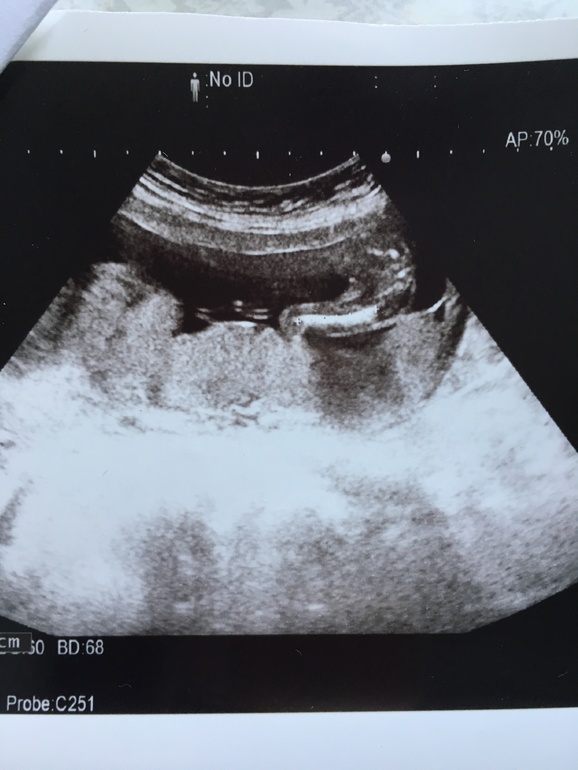

Узи в 16,5 фото на память

УЗИ, КТГ, доплервчера была на узи, уж очень хотелось узнать пол малыша. Честно, была уверена в мальчике и обращалась по имени и имя обсуждали мальчиковое, да даже одежду и расцветки коляски смотрели мальчиковые. Но в душе, мы очень хотели вторую дочку. И вчера наше солнышко показалась, очень четко было видно, что она Зоя🥰🥰🥰 мы очень рады, что у нас так получилось, мальчишки почти погодки и девочки погодки, это замечательно👏